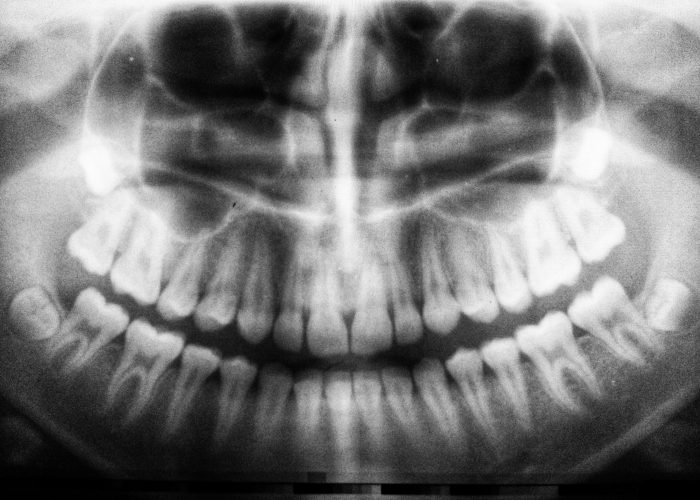

La radiographie panoramique dentaire (ou panoramique dentaire), est un type d’examen radiographique qui permet de réaliser une image en une seule prise de l’ensemble de la bouche, des dents et des structures osseuses environnantes, telles que les mâchoires, les sinus, les articulations temporo-mandibulaires et les tissus environnants. Elle offre une vue d’ensemble qui permet au praticien de mieux appréhender la santé bucco-dentaire du patient.

La radiographie panoramique repose sur l’utilisation de rayons X, mais contrairement aux radiographies traditionnelles qui montrent une seule zone à la fois, la panoramique crée une image « panoramique » de l’ensemble de la cavité buccale. L’appareil de radiographie panoramique tourne autour de la tête du patient pendant que ce dernier reste immobile et place sa tête dans une position précise. L’appareil enregistre une série de radiographies, puis les combine pour former une image complète en 2D des structures dentaires et osseuses. Cette image représente une vue d’ensemble de la bouche et des mâchoires, d’où son nom de « panoramique ».